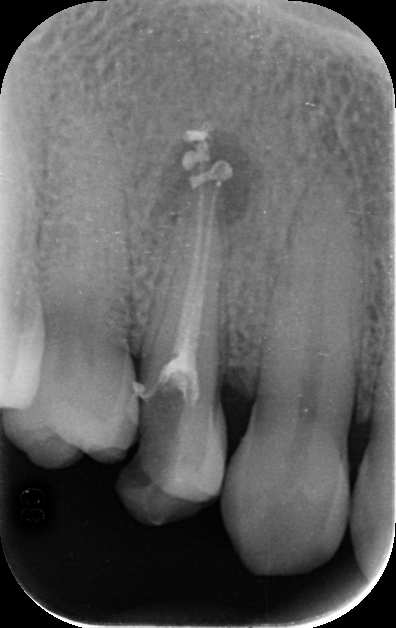

- In the first visit, I placed an intracanal medicament (calcium hydroxide) to help heal the lesion.

- After 10 days, at the second appointment, I removed the medicament and filled the canals with permanent root canal material.